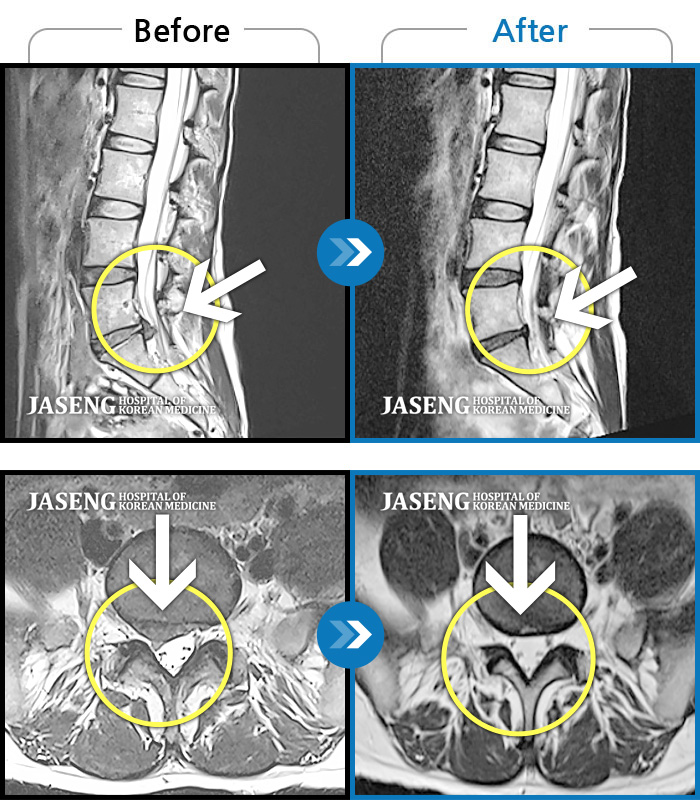

MRI 치료사례

장시간 앉았다가 서면 허리 펴기 힘들고 오른쪽 종아리가 당김